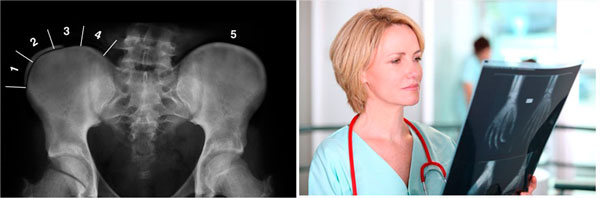

El mas usado es el signo de risser que nos permite evaluar la aparición del núcleo de osificación en la cresta iliaca

¿Cómo se determina el potencial de crecimiento óseo?

En cada visita al especialista evaluara:

- La talla de la paciente

- Además, en la radiografía puede verse el Signo de Risser, un marcador de madurez ósea visible en la pelvis y que indica cuánto queda para alcanzar la madurez ósea.

- También se tiene en cuenta la presencia de signos propios de la pubertad. En las niñas se utiliza la aparición de periodos menstruales y el desarrollo de la mama, mientras que en los niños pueden valorarse los cambios en la voz y el vello facial.

Estos indicadores de madurez ósea no siempre se correlacionan y puede ser aconsejable realizar una radiografía con objeto de evaluar los núcleos de crecimiento de los huesos de la mano y en la pelvis.